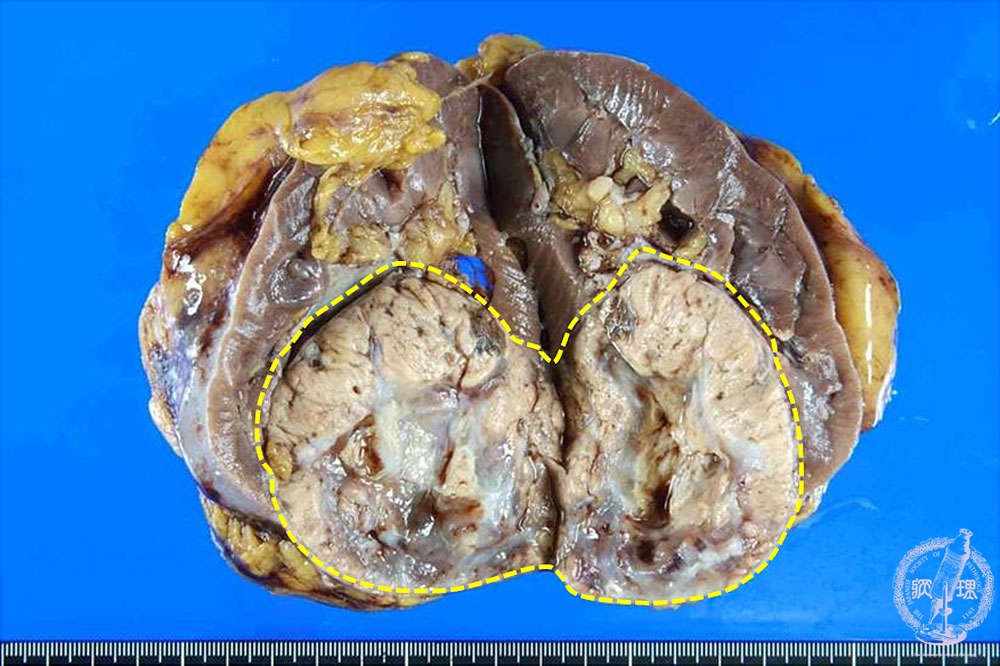

- ★(17)Renal cell carcinoma

Gross findings: Renal cell carcinoma presents a well-demarcated mass (yellow dotted line). In most cases, the tumor presents yellowish color.